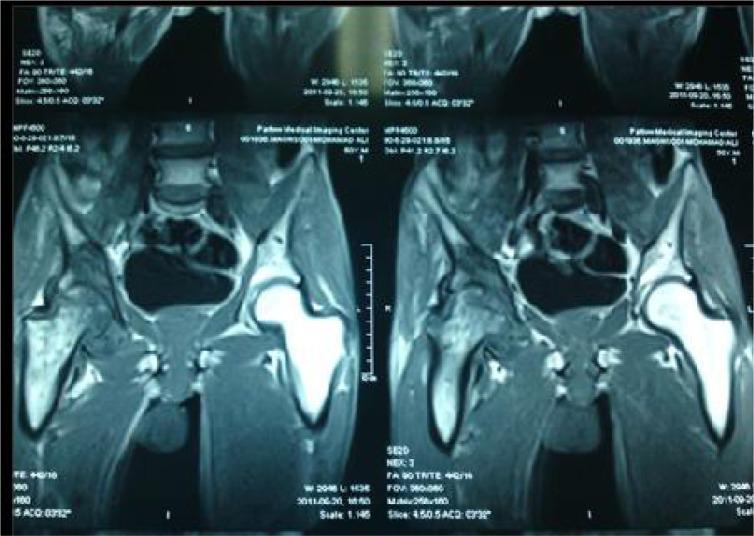

Brucellosis-induced avascular necrosis of the hip in a middle-aged person.

Femoral Head Avascular Necrosis Due to Brucella Infection: A Case Report.

Osteonecrosis of the femoral head due to brucellosis: a case report.

Brucellosis induced avascular necrosis of the femoral head in a 7 year old child.